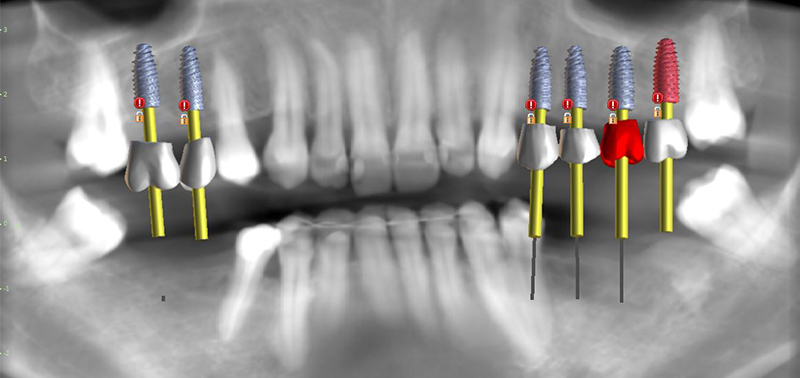

Fig. 11 : vue panoramique dents + implants.

Fig. 12 : visualisation numérique avec les douilles en place.